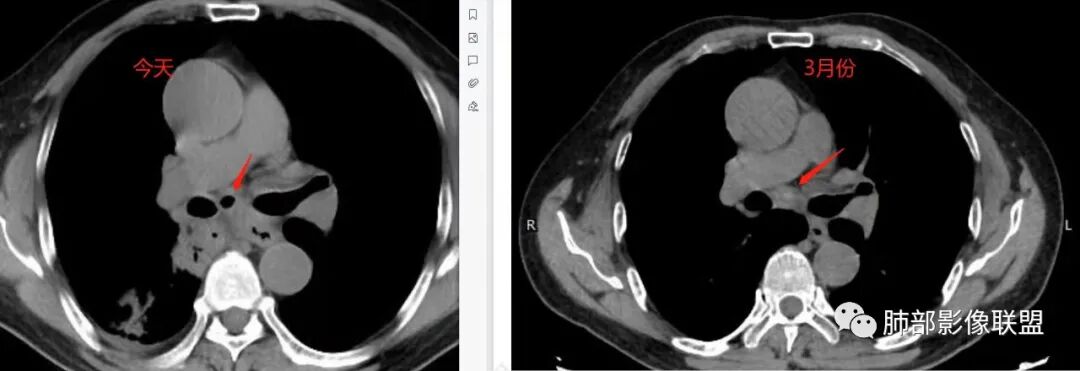

对比患者3月份的CT图,原隆突下存在增大钙化淋巴结,现在出现气体影,且钙化显示不清,应想到淋巴结结核破溃成瘘可能性。

这个病例提示我们纵隔内淋巴结伴钙化或肺内结核伴钙化,可能会因患者的免疫力下降使结核复燃。